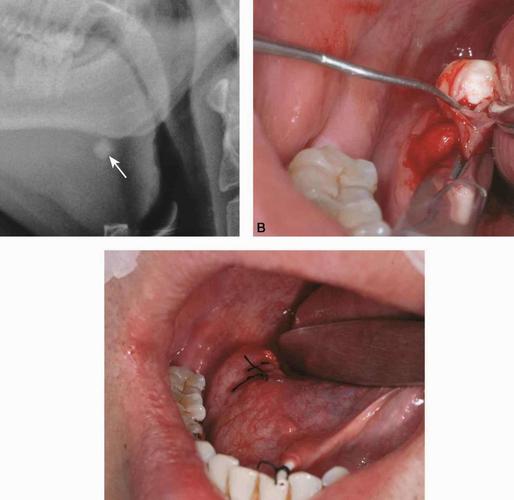

舌下腺结石图片,颌下腺导管结石图片

颌下腺导管结石图片

舌下结石

颌下腺结石位置图片

舌下腺结石CT图片

舌下腺结石手术图片

舌头下面结石图片

舌下导管结石照片

舌头下面长结石照片

颌下腺导管结石

颌下腺结石

下颌下腺结石图片

舌下腺结石

舌下腺导管结石图片